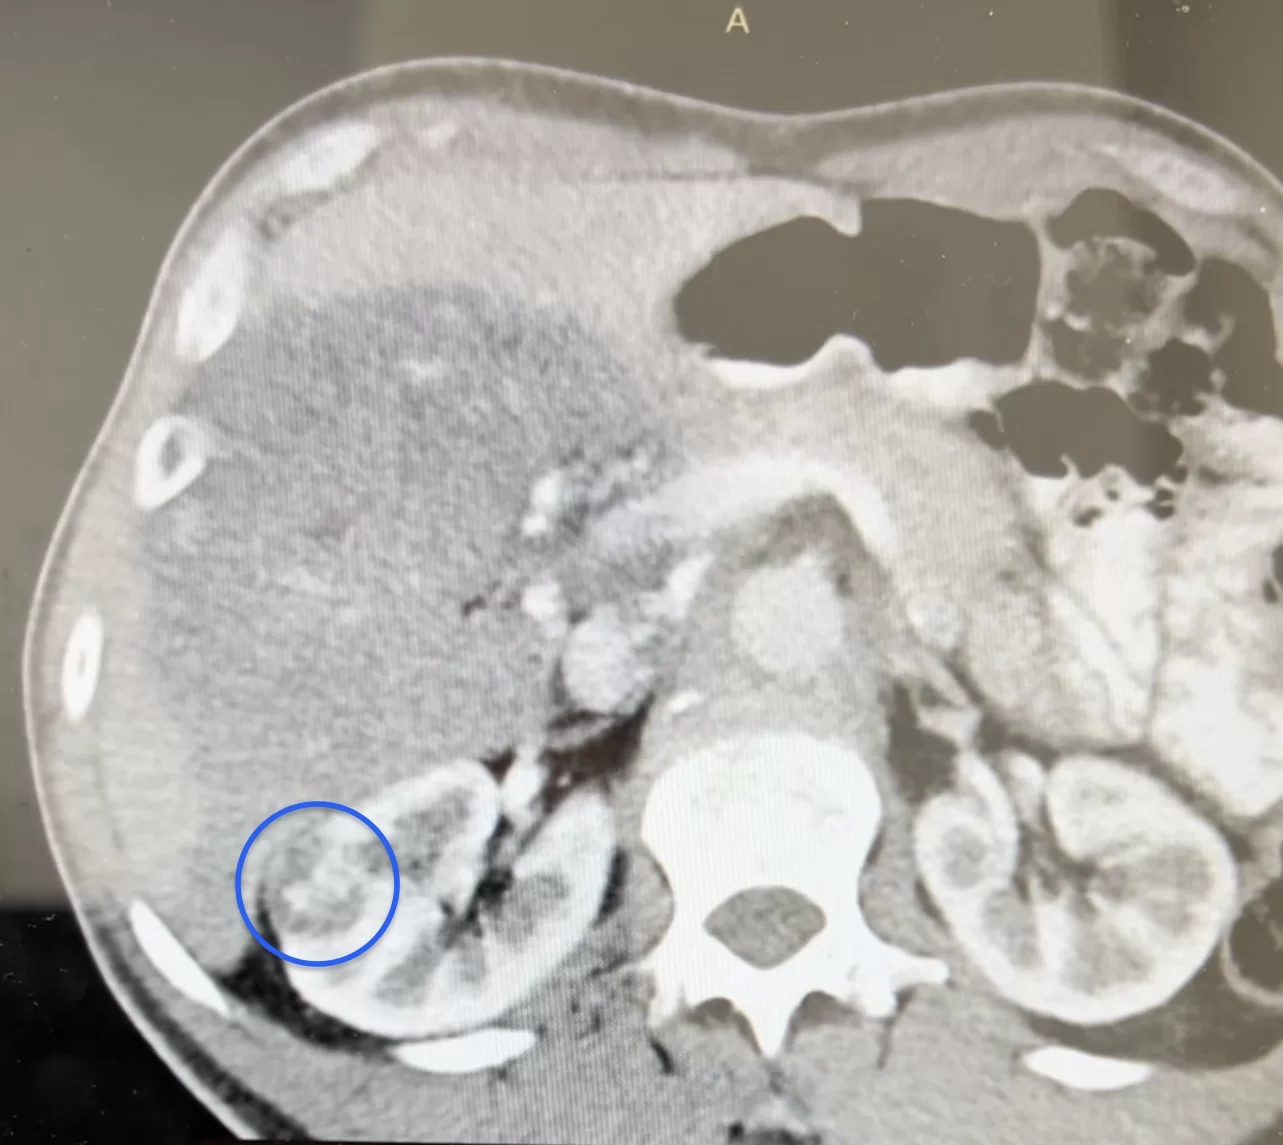

Ασθενής με όγκο νεφρού διαστάσεων 2,5 cm αντιμετωπίστηκε με μεγάλη επιτυχία από τον Dr. med. Βασίλειο Γκολεζάκη και την ομάδα του. Ο όγκος ήταν στην έξω επιφάνεια της μεσότητας του δεξιού νεφρού, μεικτής υφής (κυστικά και συμπαγή στοιχεία) και σε επαφή με περιφερικούς κάλυκες στη μέση καλυκική ομάδα του δεξιού νεφρού.